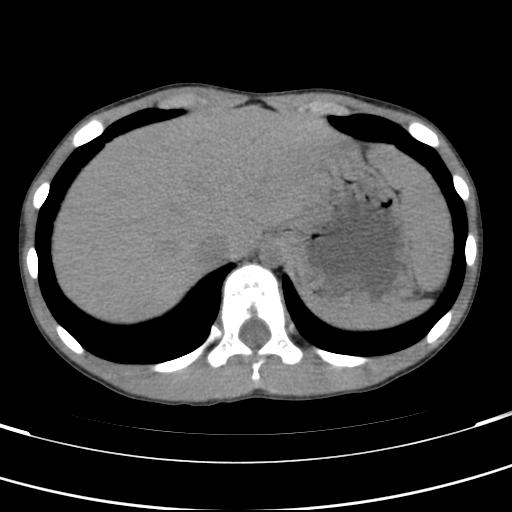

标题: PED3157:左肾缺如,请教脾脏的改变?、、

男孩,9岁。胃部不适。

脾脏位于左侧,但数个脾脏呈分离状态,左肾缺如,右肾代偿肥大。考虑多脾综合征。